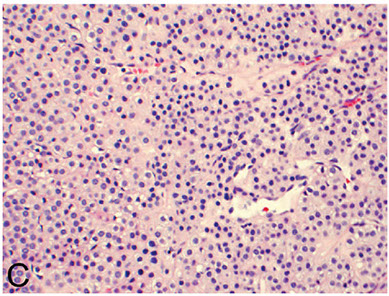

Microscopic polyangiitis (MPA)

- similar to Wegener's, but without the granulomas; lesions are of the same age (like HS purpura)

- involves lungs and kidneys and other organs, tending to affect small arterioles and venules

5) lung involvement (alveolar hemorrhage from pulmonary capillitis)

Lab: (+) pANCA (aka anti MPO; similar to Churg-Strauss)

Micro: alveolar hemorrhage, hemosiderin-laden macrophages in alveolar spaces, and neutrophilic capillaritis

MPA